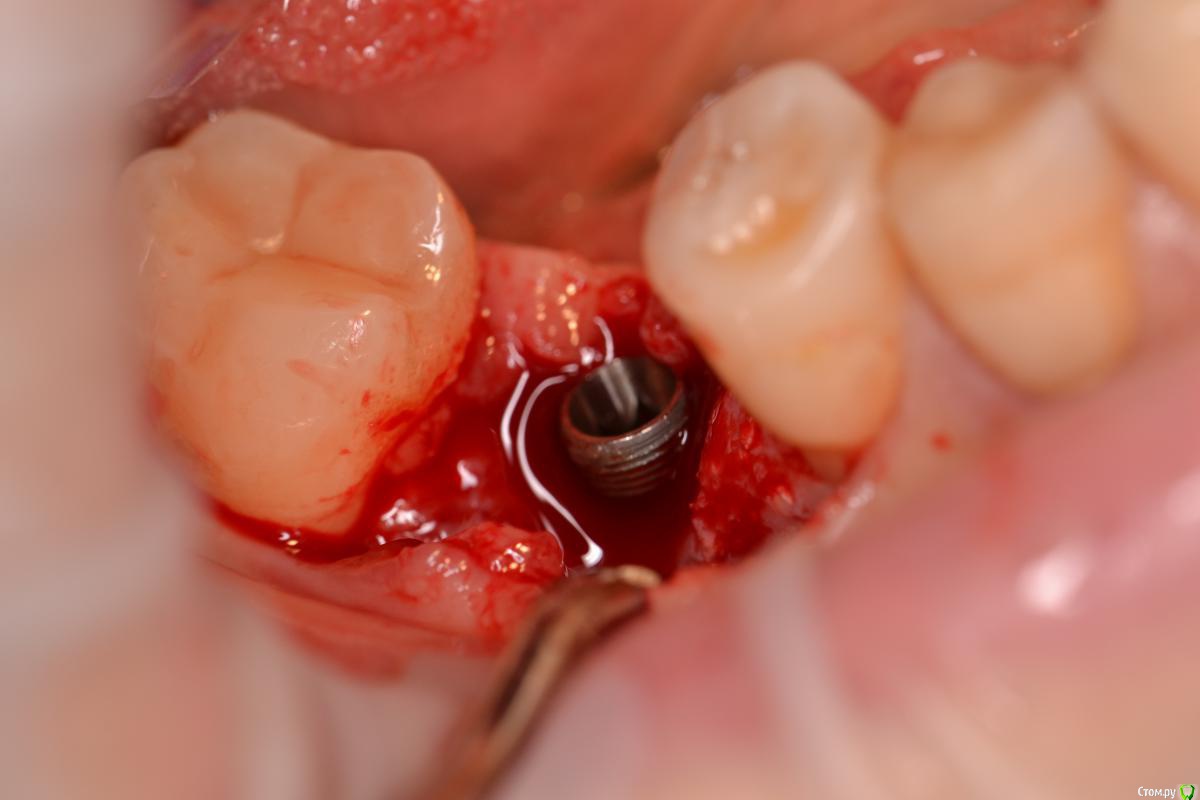

TIGER Опубликовано 22 декабря, 2016 Поделиться Опубликовано 22 декабря, 2016 Если вам сегодня нравится,что вы сделали вчера ,то вы стоите на месте....)Имплант ставил я, с виду по первому фото видно,что вроде-бы ничего...но на тот момент я бы был удовлетворён результатом,да он интегрирован,пациент доволен,отпротезировал бы,но сегодня нет...зондирование выявило резорбцию....и главное я знал,что прогноз не очень,эстетика и жизнь этого болтика...настоял на удалении...сегодня заказал набор,и на выход,сразу же имплант,заглубил,как надо)Как говорил если мне не изменяет память Эдуард Анчаков наступает эра вынимайзинга....начал со своего)P.S какое приятное чувство когда ты можешь исправить свои недочёты) 3 Ссылка на комментарий

TIGER Опубликовано 22 декабря, 2016 Автор Поделиться Опубликовано 22 декабря, 2016 Почему такое могло произойти,есть снимки после установки?Недозаглубил...банально...Снимка нет Ссылка на комментарий

surf Опубликовано 22 декабря, 2016 Поделиться Опубликовано 22 декабря, 2016 Показали бы снимок переустановленного,у заглубления тоже есть пределы,а то,может,с пластикой надо было,ну чтоб уж совсем себя порадовать А,вообще,мысль,конечно,верная! Ссылка на комментарий

TIGER Опубликовано 22 декабря, 2016 Автор Поделиться Опубликовано 22 декабря, 2016 Показали бы снимок переустановленного,у заглубления тоже есть пределы,а то,может,с пластикой надо было,ну чтоб уж совсем себя порадовать А,вообще,мысль,конечно,верная!там всё нормально)в финале выгружу 1 Ссылка на комментарий